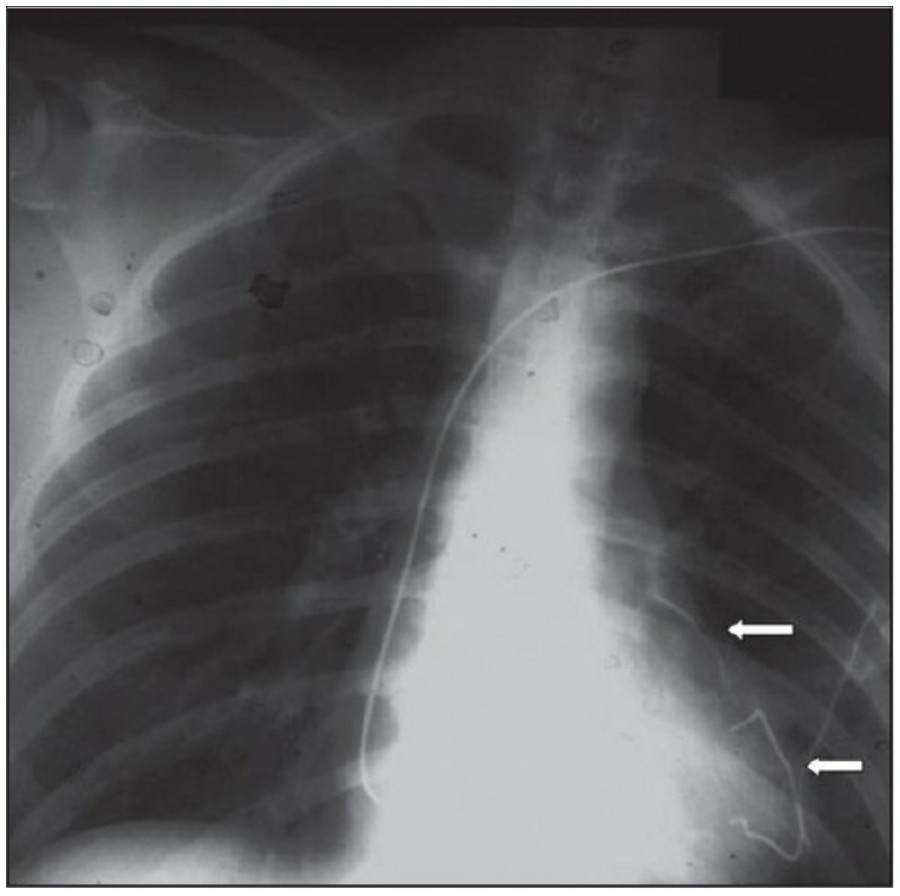

Pneumothorax

공기는 nondependent position으로 위치하므로, X ray상에서는 환자 자세에 따라 다르게 나타난다. Erect position에서 공기는 lung의 apicolateral surface에 위치하고 얇고 하얀 pleural line이 나타나며 그 뒤로 lung marking이 보이지 않는다.

하지만 pleural line 뒤로 lung marking이 존재한다고 해서 pneumothorax를 배제할 수 없다. Pneumothorax의 진단은 특히 parenchymal disease가 있을 때 진단하기 힘든데, 이는 compliance의 변화 때문에 collapse가 잘 안 되기 때문이다. Skin fold가 pneumothorax와 비슷하게 보이기도 한다.

중환자에서 pneumothorax의 진단은 종종 supine radiograph에서 내릴 수 있다. Supine position에서 공기는 anteromedial 방향으로 모이게 되는데, apical air collection이 있을 경우 large pneumothorax가 있음을 시사한다. 공기는 lung과 diaphragm 사이의 subpulmonic location에 trap 되어 있을 수도 있다. 공기가 costophrenic sulcus로 anterolateral extension 될 경우, 이 costophrenic sulcus의 radiolucency를 증가시키는데, 이를 deep sulcus sign이라고 한다. Subpulmonic pneumothorax의 다른 특징으로 diaphragm의 superior surface와 IVC 윗부분이 뚜렷하게 보일 수 있다.